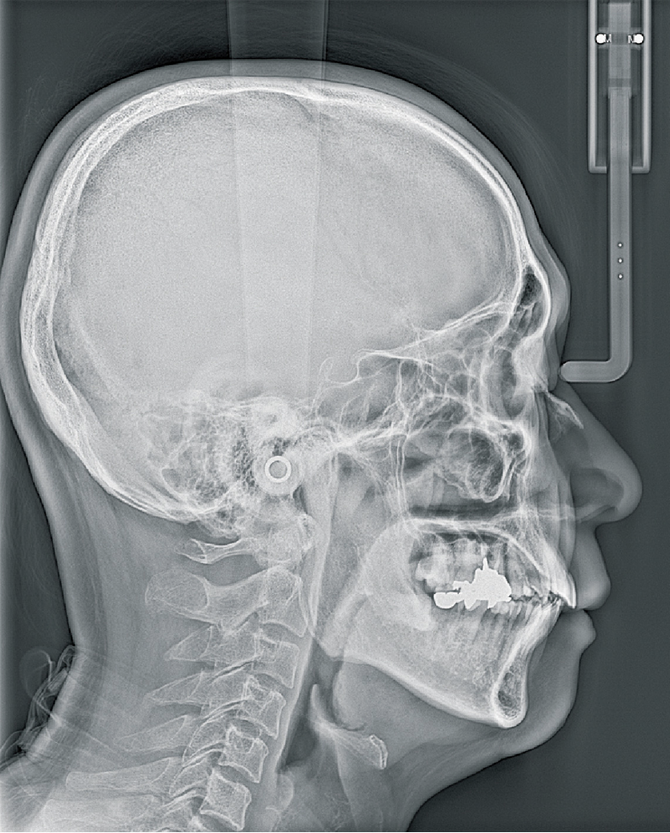

歯科撮影室:モリタ製作所 Veraview X800

セファロ2セファロ1   歯列

セファロ撮影                     歯列CT撮影